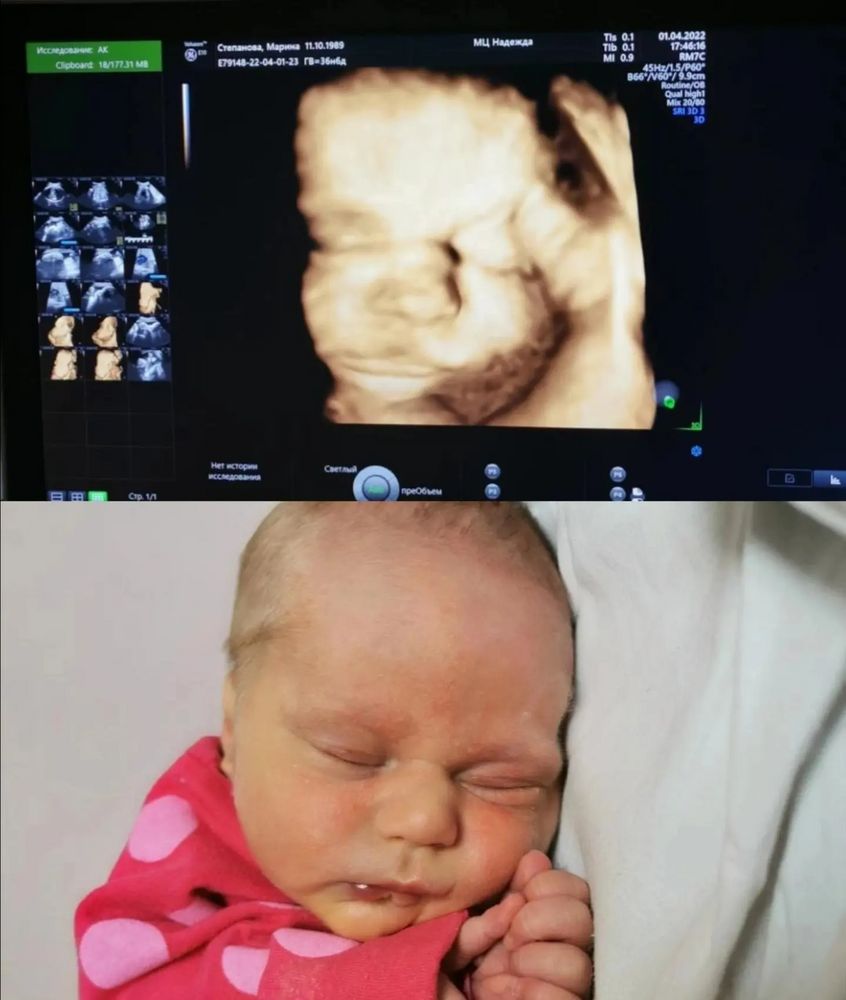

Годик моей маленькой девочке)

Изображение

До сих пор, бывает, ловлю приступы невероятности происходящего.. Неужели это мой ребёнок? Откуда? Что за Чудо такое? Да, даже с четвёртым ребёнком, как и с первым, и с кажды